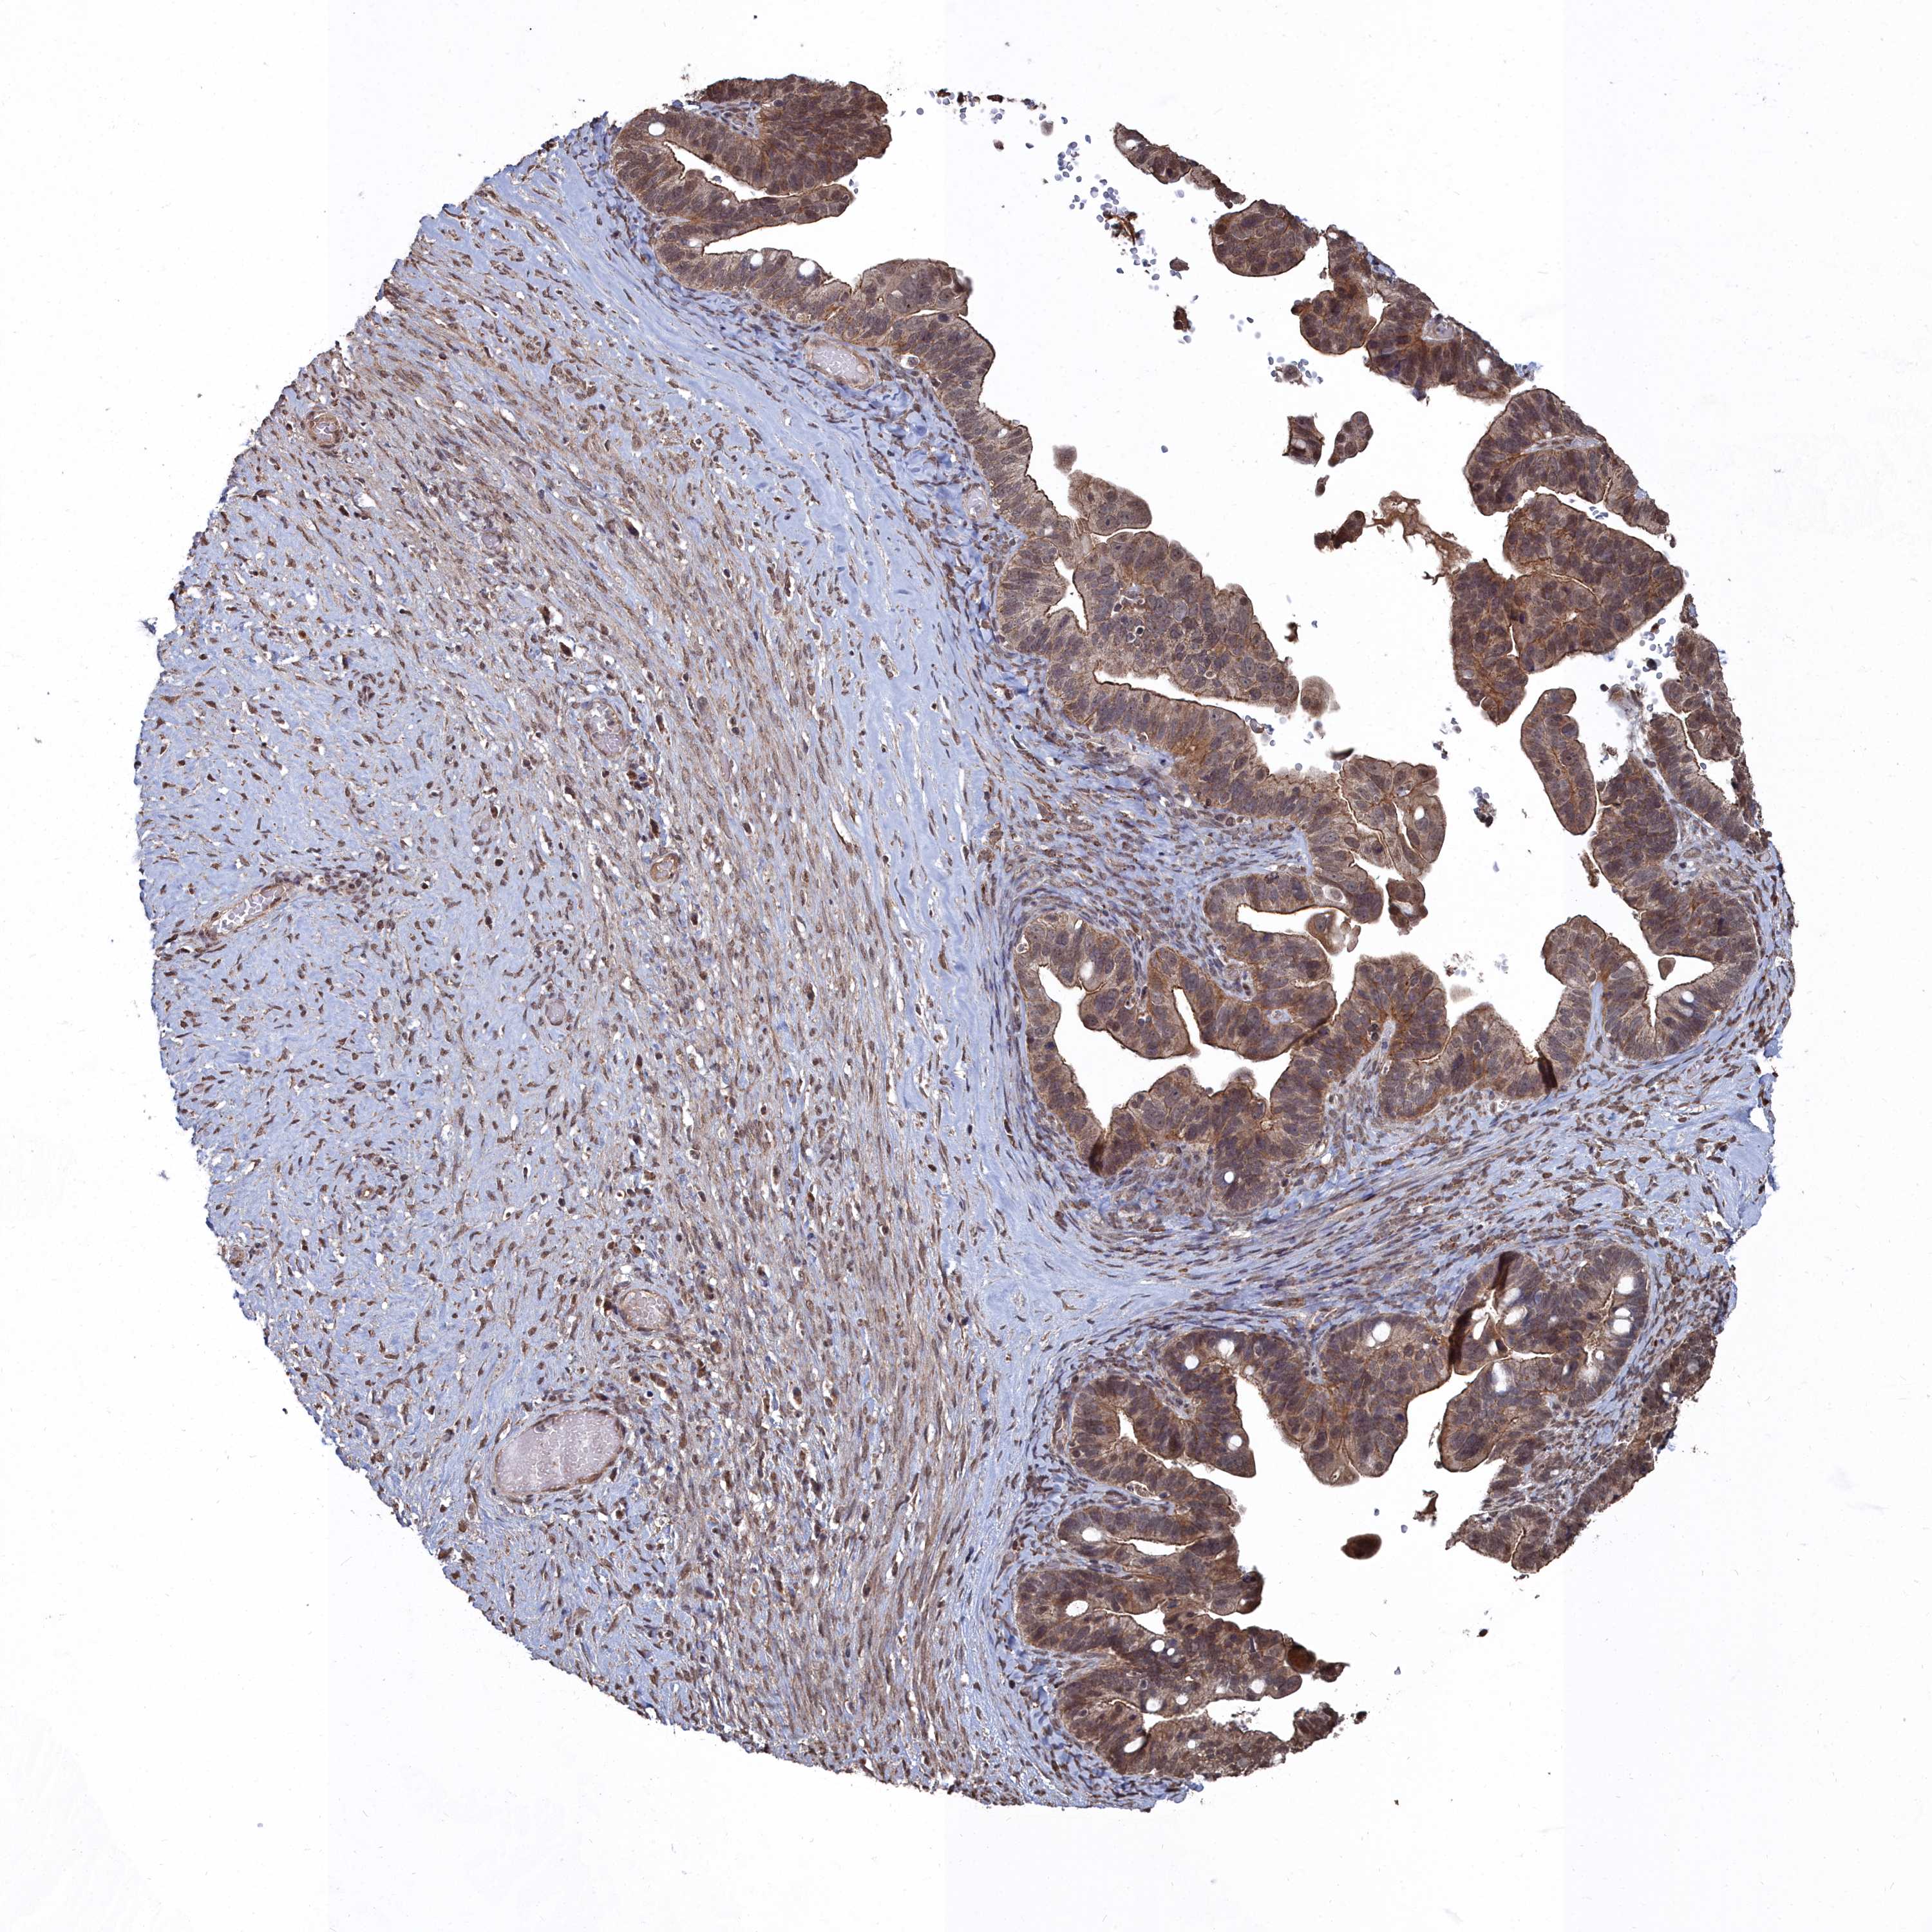

OVARIAN CANCER - Protein expressioni

A mouse-over function shows sample information and annotation data. Click on an image to view it in a full screen mode. Samples can be filtered based on level of antibody staining by selecting one or several of the following categories: high, medium, low and not detected. The assay and annotation is described here.

Note that samples used for immunohistochemistry by the Human Protein Atlas do not correspond to samples in the TCGA dataset.

Antibody stainingi

Antibody staining in the annotated cell types in the current human tissue is reported as not detected, low, medium, or high, based on conventional immunohistochemistry profiling in selected tissues. This score is based on the combination of the staining intensity and fraction of stained cells.

Each image is clickable and will lead to virtual microscopy that enables deeper exploration of all samples and also displays staining intensity scores, fraction scores and subcellular localization as well as patient and tissue information for each sample.

Antibody HPA045615

Staining

High

Medium

Low

Not detected

Intensity

Strong

Moderate

Weak

Negative

Quantity

>75%

75%-25%

<25%

None

Location

Nuclear

Cytoplasmic/membranous

Cytoplasmic/membranous,nuclear

Cystadenocarcinoma, serous, NOS

Carcinoma, NOS

Cystadenocarcinoma, mucinous, NOS

Carcinoma, endometroid